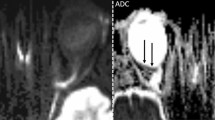

Table 1 and Fig. 1 detail retinal layer thickness measurements in CRAO patients with and without visible restricted retinal diffusion on diffusion-weighted magnetic resonance imaging. Parafoveal macular thickness measurements (SMT, IMT) of CRAO patients with no detectable RDR on DWI were significantly lower when compared to RDR+ patients (SMT: 370.5 ± 43.8 µm vs. 418.2 ± 76.0 µm, p = 0.016; IMT: 374.4 ± 42.9 µm vs. 428.8 ± 63.2 µm, p = 0.004). Central (foveal) macular thickness. however, did not differ significantly between the two groups (307.6 ± 45.8 µm vs. 344.4 ± 77.7 µm, p = 0.071). The observed differences in parafoveal macular thickness could be attributed to differences in IRLT, which were significantly lower in CRAO patients without visible RDR on DWI (188.8 ± 34.4 µm vs. 234.7 ± 49.0 µm, p = 0.002). ORLT measurements did not vary significantly (p = 0.087). Fig. 2 illustrates representative examples of IRLT measurements in CRAO patients with and without visible restricted retinal diffusion on 3T DWI-MRI.

Representative examples of IRLT measurements in CRAO patients with and without visible restricted retinal diffusion on 3T DWI-MRI (2.5 mm calculated DWI-TRACE from DTI-EPI). a, b, c No demonstrable restricted diffusion is visible on retinal DWI of a 70-year-old woman with right-sided CRAO. d The corresponding SD-OCT cross-section shows mild swelling of the inner retinal layer (182 µm, black asterisk). e, f, g A marked retinal DWI hypersignal is noted on three adjacent slices in a 67-year-old man with right-sided CRAO (white arrows). h The corresponding SD-OCT image reveals severe inner retinal layer edema (277 µm, black asterisk). CRAO central retinal artery occlusion, DWI-MRI diffusion-weighted magnetic resonance imaging, IRLT inner retinal layer thickness, SD-OCT spectral-domain optical coherence tomography, TRACE , EPI